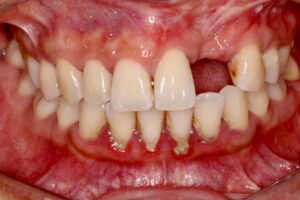

Situation initiale